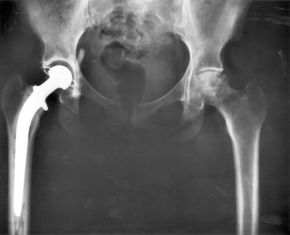

Total hip replacement surgery has become a common procedure. The head (or ball) of the patient's femur fits into a cup that has a hard plastic-like inner lining.